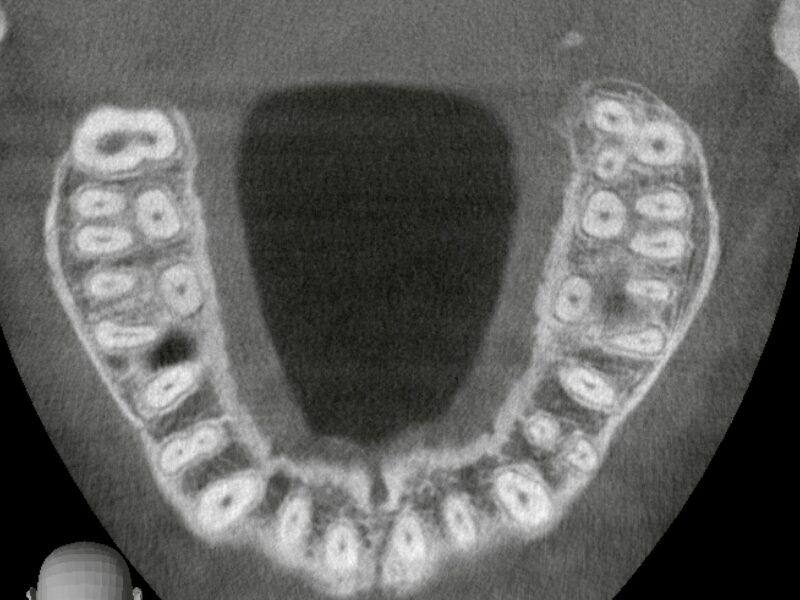

特徴4高精度診断を可能にする「歯科用CT」 -